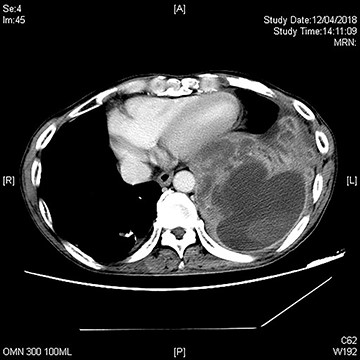

A repeat CT after TACE and PVE though showed sufficient hypertrophy of left liver, it also revealed significant growth of tumor with invasion to right lower lobe of lung through diaphragm (Fig. 1). Operation proceeded with a Mercedes-Benz incision with patient placed in supine position. Tumor was found to invade through medial part of diaphragm to right lower lobe of lung for 3 cm depth. Anterior approach right hepatectomy was performed [4]. Diaphragm was divided surrounding the tumor invasion site. En bloc wedge resection of the involved right lower lobe of lung was performed with endovascular staplers via the diaphragmatic opening. The diaphragmatic defect was closed with Goretex mesh (Fig. 2). Patient made an uneventful recovery and went home on Day 8 after surgery. Pathology confirmed a 12.5 cm poorly differentiated HCC invading through diaphragm to lung (Figs 3 and 4). Both resection margins at liver and lung were >1 cm. AFP decreased to 3 μg/l after operation.

CT showing a large hepatocellular carcinoma invading through diaphragm into lung base. (A) axial view, (B) coronal view and (C) sagittal view. Hyperdense material within liver is lipiodol deposits after previous TACE.